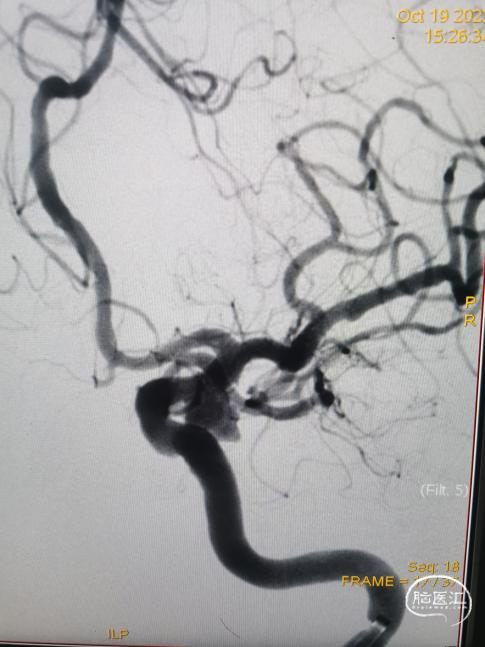

DSA:右侧颈内动脉交通段见一动脉瘤,瘤颈约4.3mm,瘤体大小约7.9mm*6.9mm,后交通动脉自瘤体发出,左侧颈总造影未见明显异常。左侧椎动脉造影基底动脉及其后显影不良,右椎造影,压颈后造影,大脑后动脉显影良好,可见造影剂返流至动脉瘤瘤体内。

椎动脉造影。

右椎造影

压颈椎动脉造影